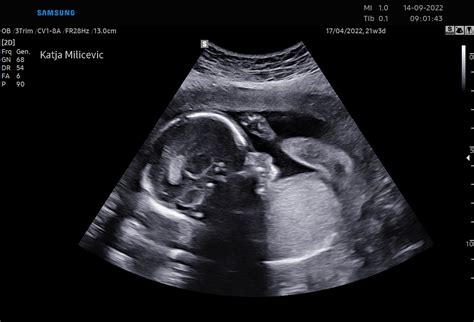

- teden nosečnosti je ključen za nadaljnji razvoj ploda. Zanj se začenja najintenzivnejša faza rasti. V tem tednu se začnejo razvijati kompleksne funkcije otrokovih organov. Tudi zametki organov, ki so značilni za posamezni spol (ženski ali moški), že obstajajo in se bodo naslednjih nekaj tednov razvijali, čeprav bo trajalo še nekaj časa, preden boste izvedeli, ali je vaš otrok fantek ali deklica. Kožice, ki je na začetku povezovala posamezne prste na rokah in nogah, ni več in otrok se že lahko igra s prsti na rokah ter poskuša dati palec v usta. Ob nastanku celic se razvijejo različne plasti otrokove kože, ki je tako čedalje debelejša in zaradi tega tudi manj prosojna kot prej. Korenine las se razvijejo v drugi plasti kože, imenovani dermis ali usnjica, od 13. tedna naprej pa se pri otroku pojavijo drobne, fine dlake, imenovane lanugo, ki skoraj v celoti pokrijejo njegovo telo in ga zaščitijo. Vsaka korenina ima tudi lojnico, ki proizvaja maščobno, vodoodporno snov, imenovano verniks ali sirasta maz. Lanugo verniksu pomaga, da prekrije otrokovo telo, skupaj pa igrata pomembno vlogo: preprečujeta, da bi otrokova občutljiva koža v plodovnici postala preveč mehka, delujeta kot učinkovita toplotna izolacija in nudita zaščito pred vibracijami, zvoki in pritiski.

V 11. tednu nosečnosti se žensko telo prav tako že prilagaja na novo stanje. Najverjetneje se počutite že veliko bolje. Obdobje slabosti bi moralo biti mimo, tveganje za spontani splav je zdaj zelo majhno, zato ste verjetno tudi precej mirnejši. Če tega še niste storili, lahko začnete razmišljati, kdaj in kako boste svojim bližnjim zaupali veselo novico o nosečnosti. Nosečniškega trebuščka še ni videti, če pa je to vaša druga ali tretja nosečnost, vi sami morda že opazite njegove zametke. V vsakem primeru ste že začeli pridobivati na telesni teži, saj si telo dela maščobne zaloge. Ni razlogov za zaskrbljenost, z malce športa ali telesne vadbe ter zdravo prehrano se boste po porodu znebili dodatnih kilogramov, dojenje pa bo prav tako pomagalo, da se vrnete v dobro telesno kondicijo. Zadnji tedni nosečnosti so lahko zelo naporni, zato morate že vnaprej delati na moči in poskrbeti, da ostanete v dobri kondiciji. Zaradi rasti maternice se lahko občasno pojavi občutek, kot bi vas nekaj vleklo v trebuhu. Med telesno vadbo, pa tudi med sedenjem ali ležanjem na eni strani telesa, se lahko pojavijo bolečine v hrbtu, saj so vaše kite zdaj bolj razrahljane in prožne, da lahko prenesejo povečano telesno težo. Telesna aktivnost med nosečnostjo je torej zelo pomembna, še posebej če ste bili pred zanositvijo športno aktivni. V naslednjih nekaj tednih bodo vaše dojke še naprej boleče, bradavice pa občutljive.